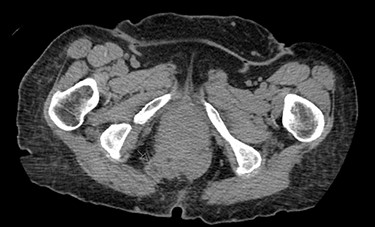

A 62-year-old post-menopausal female presented with worsening fecal urgency, incontinence and a corresponding perianal bulge that was increasing in size over the past 2 years. The patient had a recent history of significant weight loss through diet modification. Medical history was significant for two previous vaginal deliveries, 15-pack per year smoking history, hypothyroidism, hiatal hernia, previous CVA and chronic obstructive pulmonary disease. Fifteen years prior, the patient underwent a total vaginal hysterectomy, including a McCall culdoplasty, anterior and posterior repairs, sacrospinous ligament suspension and tension-free vaginal taping to treat symptomatic cystocele, rectocele and descent of the uterus. A previous computed tomography (CT) demonstrated a heterogeneously enhancing mass extending from the right posterolateral margin of the lower vaginal cuff and perirectal region into the ischioanal fossa, suggestive of, but not definite for a soft tissue mass (Fig. 1). Upon clinical exam, the patient was noted to have a defect in the right levator muscles complex with complete herniation of her rectum through this defect. This hernia created pocking of the stool and difficulties with stool emptying. In addition, the patient had to adjust her sitting position to avoid unwanted stool leakage as a result of spontaneous hernia reduction. The patient was offered an abdominoperineal resection; however, discussion of laparoscopic interventions with the DaVinci robot quickly became the best option for repair. Informed consent was obtained for robotic repair, and routine preoperative colonoscopy was performed.